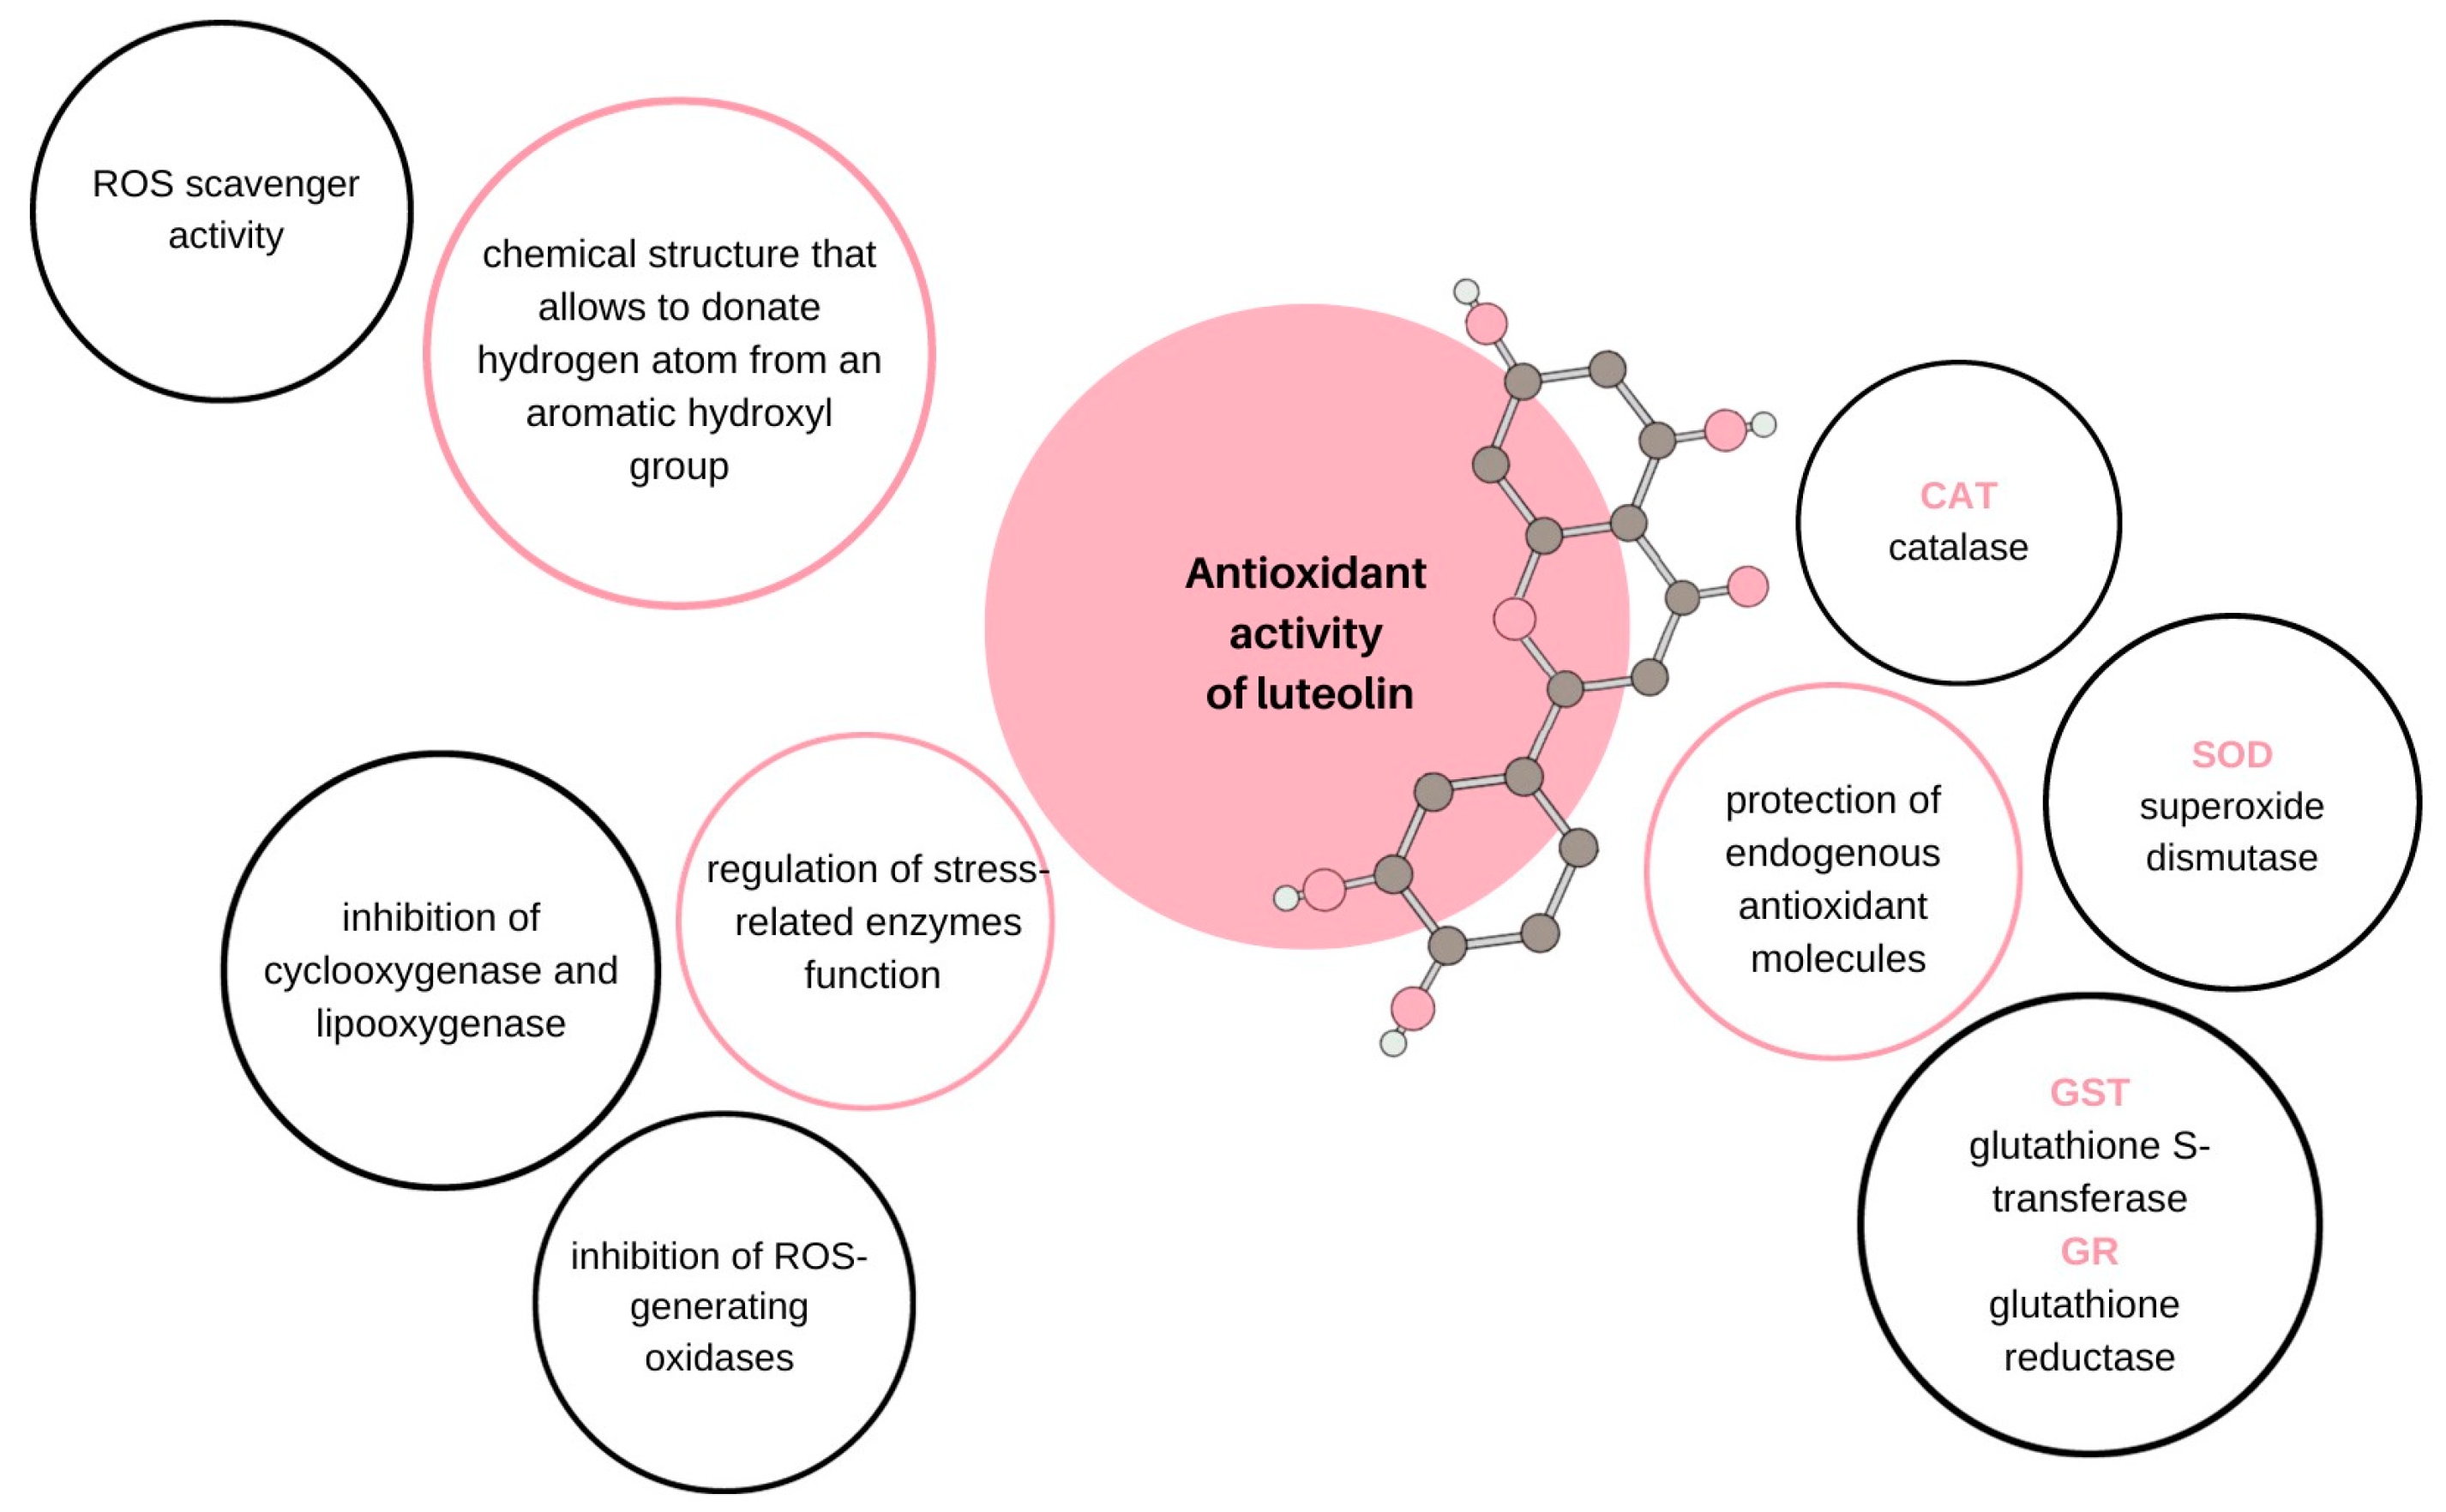

:1. Introduction